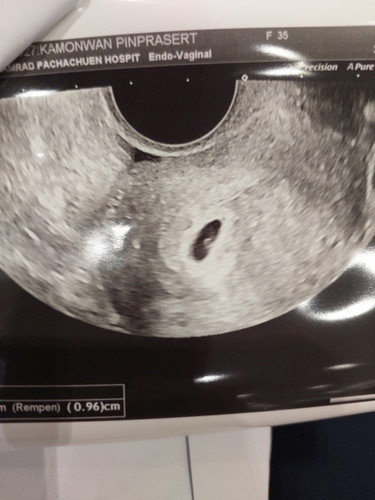

ถุงครรภ์ขนาด 5 สัปดาห์

ถุงครรภ์ขนาดประมาณ 1 เซนติเมตรสำหรับอายุครรภ์ประมาณ 5 สัปดาห์เล็กไหมคะแม่ๆ#ขอบคุณล่วงหน้านะคะ #ขอบคุณสำหรับคำตอบค่ะ

ขนาดปกติจ้า แต่หมอจะไม่นับขนาดถุงนะคะ 1.หมอจะดูว่าถุงนั้นมี-ไข่แดงไหม 2.พอมีไข่แดง-หมอก็จะมารอดูว่ามีตัวอ่อนไหมค่ะ 3.พอมีตัวอ่อน-หมอก็จะมารอดูว่ามีหัวใจไหมค่ะ 4.พอเจอหัวใจ-หมอก็จะมาดูว่าหัวใจเต้นไหม และจังหวะเต้นปกติไหมค่ะ จะเป็นแบบนี้ตามสเต็ปค่ะ

อ่านเพิ่มเติมรอลุ้นว่าจะมีตัวอ่อนมั้ยดีกว่าค่ะ เค้าไม่นับนะคะความใหญ่ของถุงตั้งครรภ์น่ะคะ 😁